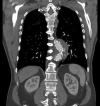

Persistent false lumen flow is common after thoracic endovascular aortic repair of type B aortic dissection and may contribute to continued aortic aneurysmal degeneration. We report an innovative technique of intercostal artery embolization within the false lumen for a patient who had incomplete false lumen thrombosis and progressive aortic enlargement after thoracic endovascular aortic repair of chronic type B aortic dissection. Technical success was facilitated by use of on-table cone beam computed tomography angiography, virtual vessel marking, and modern endovascular tools. The patient had no complications from the procedure. Postoperative imaging demonstrated complete thoracic false lumen thrombosis and favorable aortic remodeling with reduction in maximal aortic diameter.